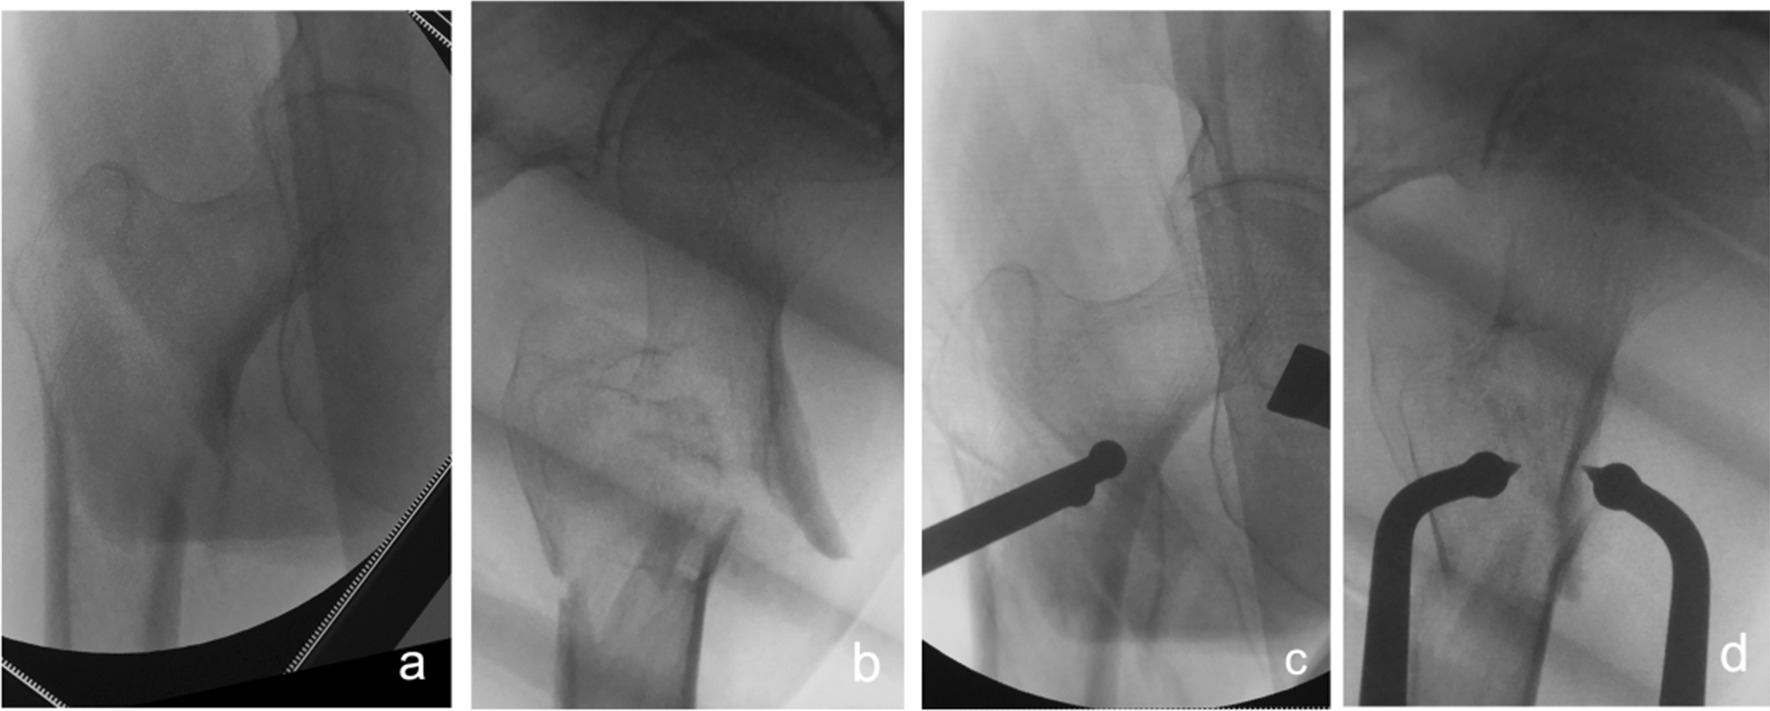

Fig. 4.

Anteroposterior and lateral X-ray films before and after reduction in patients with difficulty in reduction on the sagittal plane and supination displacement of the proximal fracture segment a, b Before reduction; c, d After reduction